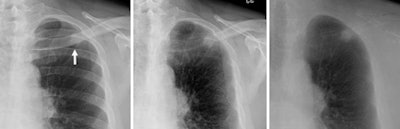

![]() |

| In the MacMahon et al study, radiologists rated a small pulmonary nodule (< 20 mm) as more conspicuous on a bone suppression image (left) than on standard chest radiograph (center), where it was partly obscured by overlying bones. Dual-energy subtraction (right) provided the most complete bone subtraction but required special equipment to perform. Images courtesy of Dr. Heber MacMahon. |

A receiver operator characteristics (ROC) statistical analysis found that reading accuracy followed the same pattern. Bone suppression via software led to more accurate diagnoses than standard x-rays, but hardware-based dual-energy imaging was even more accurate.